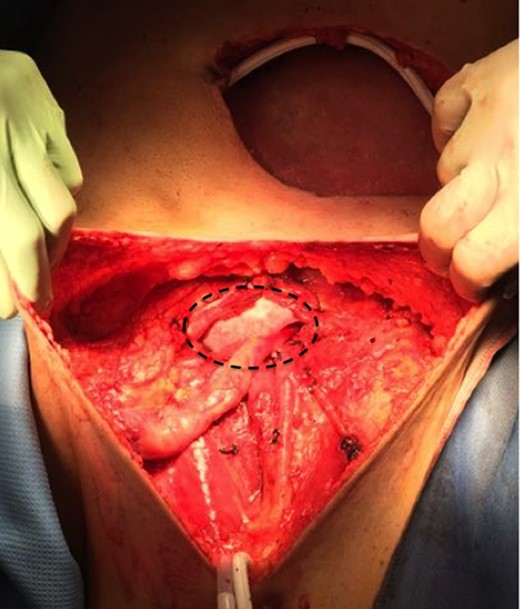

Then a right mastectomy with third level axillary lymphadenectomy, for sentinel lymph node positivity; removal of the left abdominal mass with resection of the band of external oblique muscle and of the infiltrated anterior inguinal wall; lymphadenectomy of the external and common left iliac artery; deep and superficial left inguinal lymphadenectomy (Fig. 2) were performed. Reconstruction of the abdominal band and of the inguinal canal wall was obtained using a GORE® BIO-A® prosthesis (Fig. 3).

GORE® BIO-A® prosthesis used for reconstruction of the abdominal wall and inguinal canal.

Gore BIO-A has a manageable structure that allows it to be positioned and shaped according to needs, its strength provides for excellent support for the reconstruction of the inguinal canal wall (Fig. 3) as in our case, where the front wall of the inguinal canal and the external inguinal ring have been removed for neoplastic infiltration.